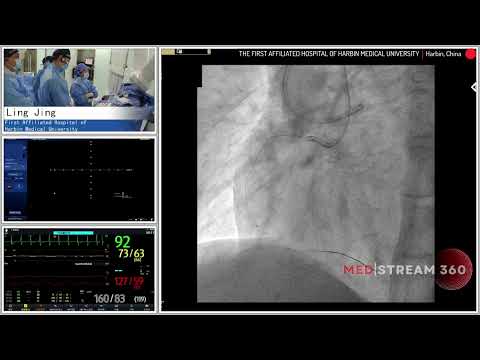

PCI of CTO RCA using Antegrade/Retrograde Approach - November 20, 2012 Webcast Video

PCI of RCA CTO using Antegrade or Retrograde Approach - July 17, 2018

Recanalization of a complex RCA CTO using Antegrade/Retrograde Approach

Recanalization of a complex RCA CTO using Antegrade Retrograde Approach - Oct 2019

Staged PCI of RCA CTO using Antegrade/Retrograde Approach - November 2022

PCI of mid RCA CTO via Antegrade/Retrograde Approach - December 2022